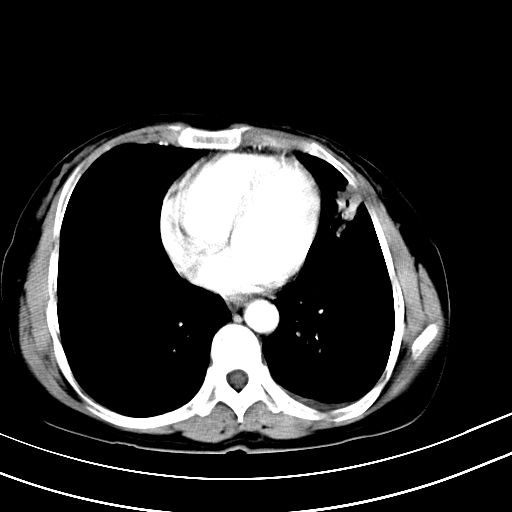

女,47岁,咳嗽胸痛一个星期,我们考虑肺结核,左下肺病灶肿瘤像不像,请高手指点。急。

右肺上叶尖后段班片影不能出外肺结核。左肺舌叶三角形实变影,增强明显。考虑炎性病变

左上肺舌叶实质性病变,形态呈楔形,内可见支气管气像,中至重度强化,考虑为炎性改变,建议复查

1)右肺上叶前段及左肺上叶舌段感染性病变;建议抗炎治疗后复查。2)左侧少量胸腔积液。

考虑右肺上叶前段及左肺舌叶炎症,建议抗炎治疗后复查除外结核。

左肺舌叶病灶呈扇形分布,其内可见支气管影,胸膜面光滑,不支持肿瘤病变。